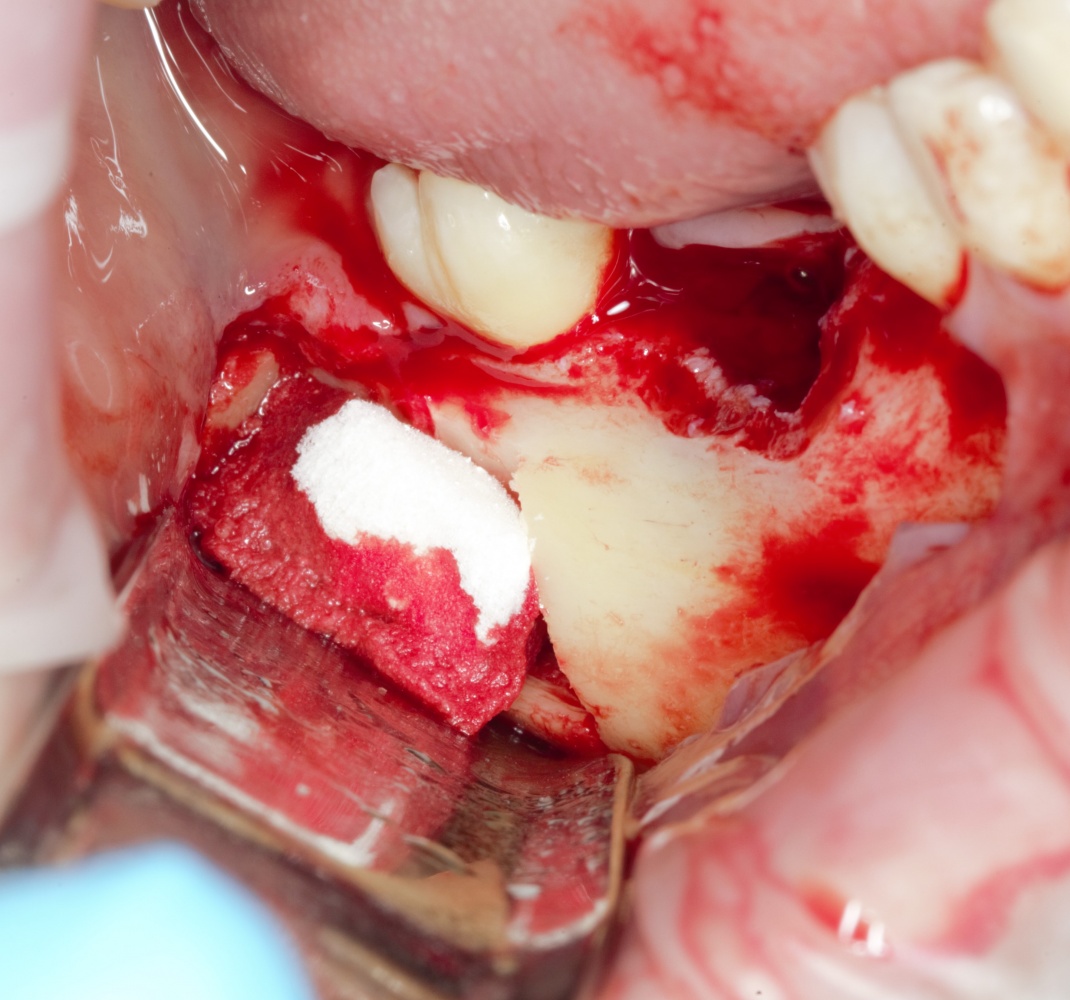

Простой. Надежный. Дешевый. Способ остеопластики.